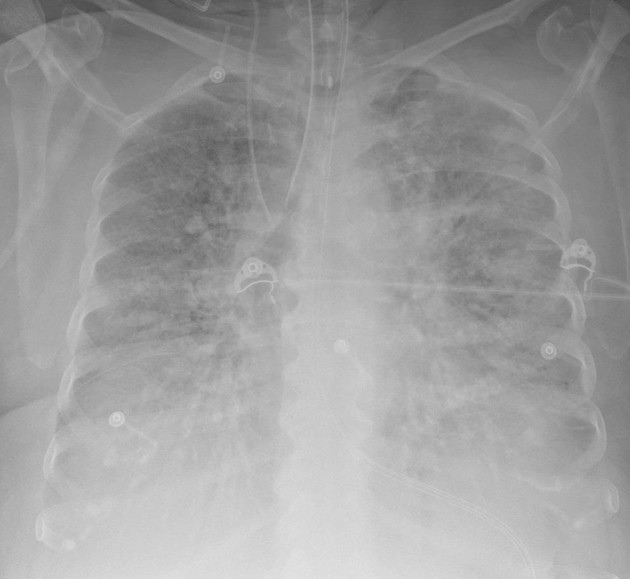

Your patient's AM CXR. Vent changes that you anticipate (2 important ones)

High PEEP and low tidal volumes